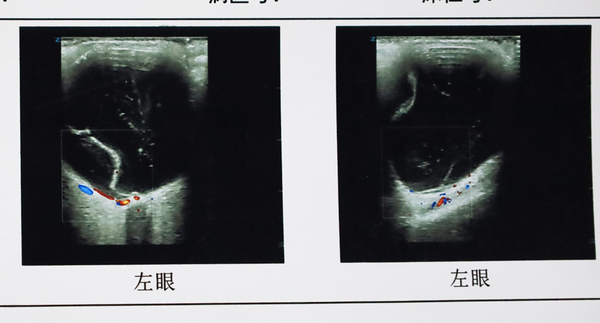

经李院长详细检查,张女士存在“左眼孔源性视网膜脱离”。更麻烦的是脱离网膜已波及黄斑区,导致视力急剧下降,仅剩手动/30cm,和失明无样,走路需要人扶。

在40分钟左右时间,张女士的手术顺利完成。术后经过一段时间的精心休养和康复,张女士左眼的视网膜复位良好,已经可以看到0.25了,这对1200度近视的视网膜脱离患者显得难能可贵。